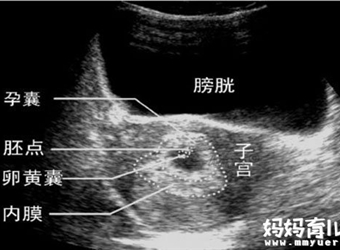

孕早期,想要了解胎儿发育情况,就需要通过做B超来看。B超中包括孕囊、胎心、胎芽等数据。不同的数据反映出胎宝宝不同的发育指标,而孕早期我们可以通过孕囊大…